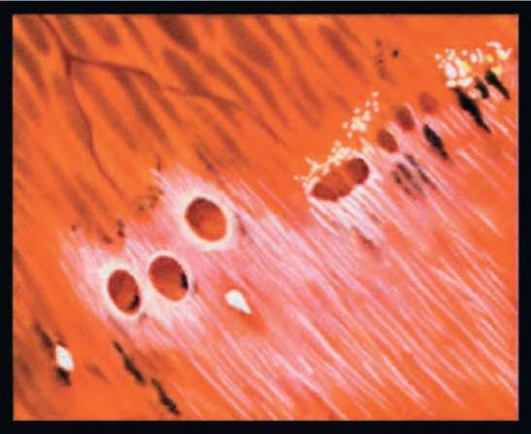

Рис. 26.2. Гранулематозный токсоплазмозный хориоретинит